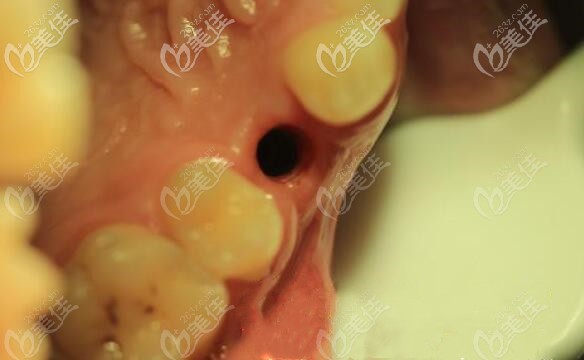

手术过程也很快,当然一部分是因为医生技术成熟,还有一部分是因为顾客的配合。

手术时间也就把半个小时就完成了,当天为顾客戴临时冠,